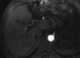

Hypervascular prostate lesion